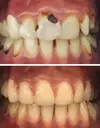

تسوس الأسنان

تطبيقات الزركونيوم

علاج الزرع السني